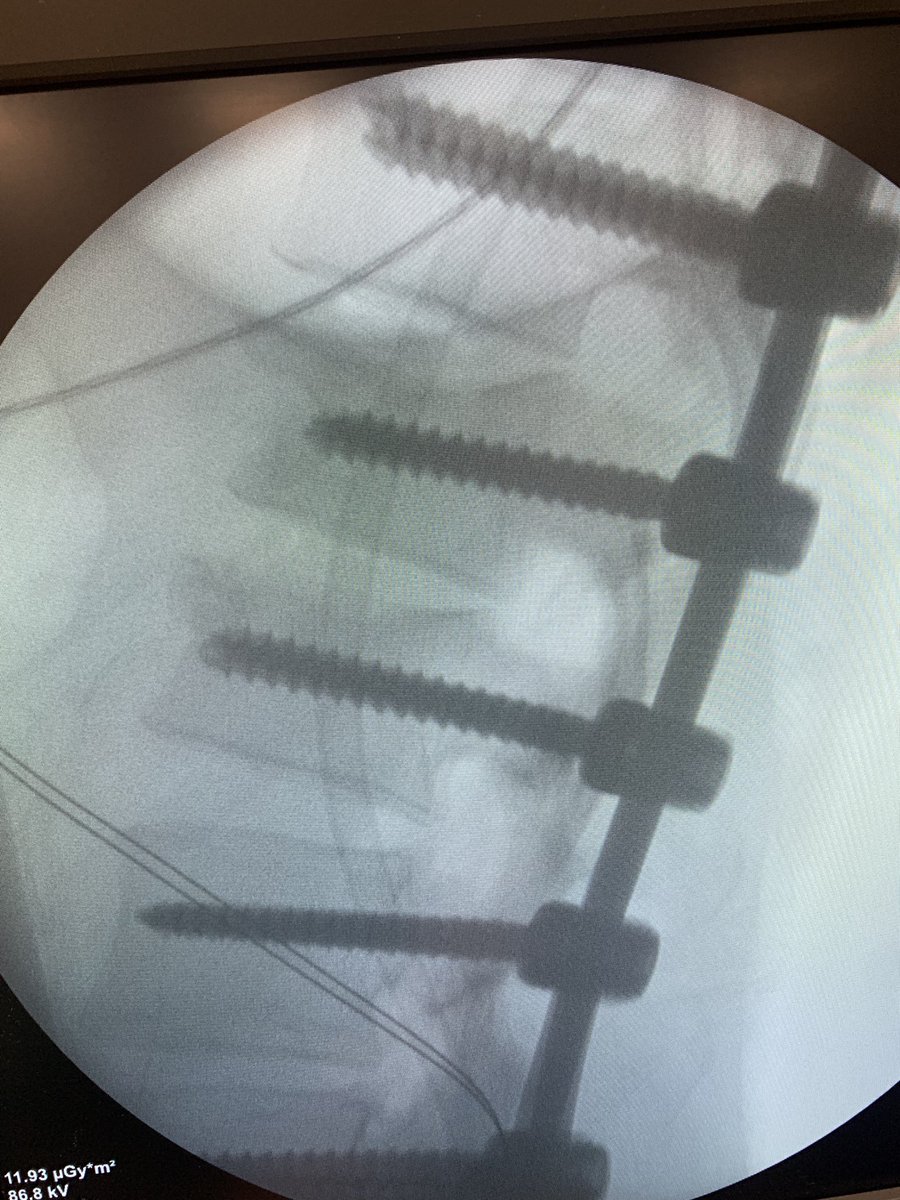

10 y o male, congenital kyphosis case. treatment with kyphectomy and double fibula allograft. #spinesurgery #spine

47 years old male patient, neglected (3 mounths) multilevel thoracolumbar junction spine fracture (L1, T12 and endplate of T11). there is monosegmental pure osseous failure of the posterior tension band in T12. this also called "Chance" fractures. #spinesurgery #spine